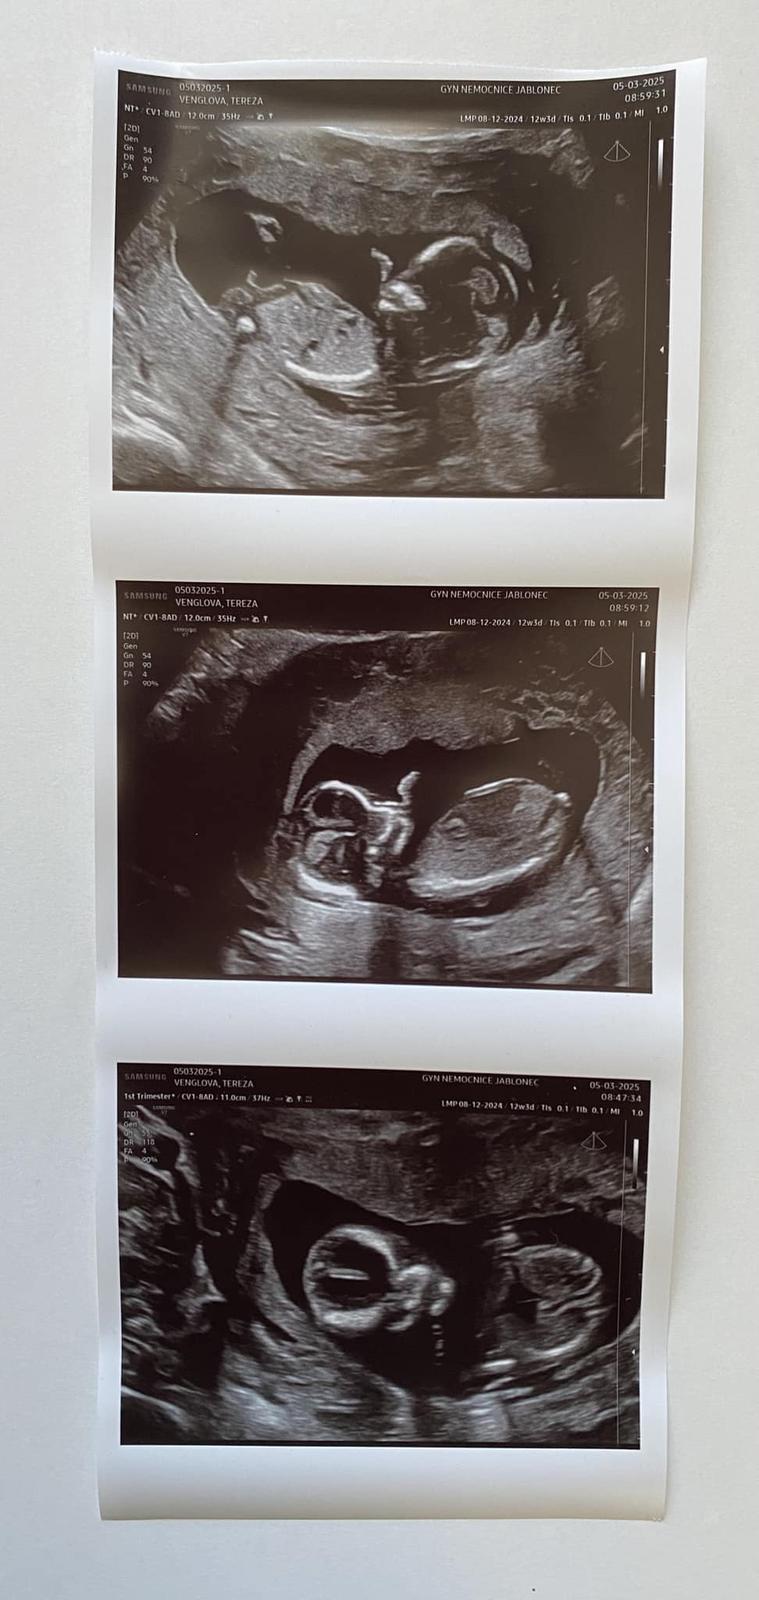

Pohlaví dítěte z ultrazvuku. Poznáte?

@martina1317 moc děkuji! On mi totiž každej tvrdí, že tý trojfotce na tom prvním obrázku je vidět pindík, ale podle mě je to nožička...

Dobrý den. Na ultrazvuku byl vidět ,, pindík, vrchem a stal🙈 Doktor řekl že tipuje kluka a za 3 tydny to pry bude vidět líp. Mam doma 4 holky🙈🤣 nepoznáte to Podle hrbolku nějakého? 🙈